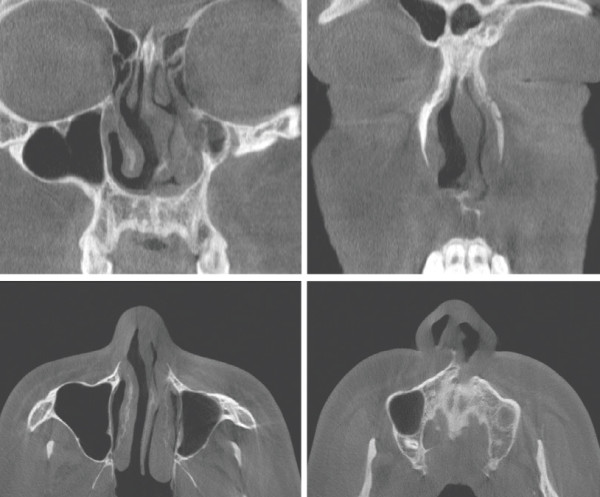

수술 전 CT. 좌측 비중격 부위의 bone 결손과 비중격의 전반적인 좌측 만곡, 비밸브 협착이 관찰되었다. 이러한 뼈의 결손은 비중격의 상악 부위에서도 함께

확인되었다

Cottle test에서 좌측 positive가 관찰되었으며, 흡기 시 우측 비익연골의 허탈 소견을 보였다. 내원 당 시 시행한 CT상 occult cleft lip and palate와 좌측 maxilla 일부의 결여를 보였으며, nasal spine 좌측 이 소실되어 있었다. 비중격 상단에서 골부에 걸쳐서 좌측으로 high septal deviation 소견을 보였으며, 우측 caudal septum이 좌측으로 심하게 전위된 결과 가 관찰되었다. 또한 비익연골의 내전과 비중격 미단부 변형으로 인한 좌측 비밸브 협착도 보였다